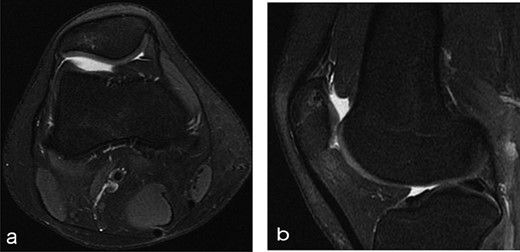

A 14-year-old female dancer presented with increasing right knee pain and functional disability without any trauma. Her pain was retropatellar pain that often radiated medially or laterally from the patella, exacerbated by climbing stairs, running and squatting. She was unable to perform any sports activities. Examination revealed peripatellar tenderness and crepitus, full range of motion and the knee was stable. Radiological examination included both MRI and computed tomography of the knee were performed at the beginning. MRI showed osteochondritis dissecans at the area at the superolateral facet of the patella in the deep subchondral area as shown in Fig. 1. This was appropriately treated conservatively with 6 months of reduced load and protected weight bearing without relief of symptoms. She quit sport activity for 2 years and then another MRI was performed Fig. 2. After 2 years we opted for adipose-derived mesenchymal stromal cells (AD-MSCs) intra-articular therapy according to the procedure described by Tremolada et al. [9]. The patient’s parents were given written information regarding the use of AD-MSCs therapy, including relative risks of this therapy and also relevant treatment alternatives that could otherwise be explored. Postoperative radiological evaluation was performed at 6 months and 12 months after AD-MSCs procedure as shown in Figs. 3 and 4. Postoperative clinical evaluation was performed using IDKC, Lysholm and Tegner scores (Table 1). After surgery, patients began a McConnell program of lateral retinacular stretching, patellar taping and vastus medialis obliquus muscle exercises. The patient was encouraged to swim and cycle to reduce impact loading. Using AD-MSC, she reported a complete relief of pain after 1 year from the procedure. Routine MRI follow-up 2 years later showed evidence of appreciable improvement in cartilage volume and osteochondral architecture at the site of injury. Early MRI T2 mapping at 6 months indicated that the area of cartilage regeneration exhibited high water content suggestive of immature cartilage or fibrocartilage morphology. Later T2 mapping at 18 months after the procedure, indicated progressive maturation of cartilage from deep to superficial layers with more hyaline like cartilage morphology. Limitations of the study are lack of arthroscopic intra-articular visualization and classification of the patella lesion.

Twelve months after MSC treatment in (a) axial and (b) sagital T2-weighted of MRI T2 sequences the OCD in patella showed that area was almost regenerated with good fibrocartilage morphology.